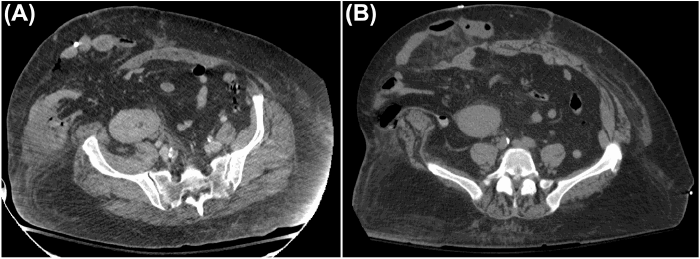

After multidisciplinary discussions involving minimally invasive surgery, plastic surgery, and transplant surgery teams, a combined procedure for definitive hernia repair with component separation and panniculectomy was planned. Approximately 22 months after her kidney transplant and 12 months after her bariatric surgery, the patient presented for this definitive repair. Preoperative axial CT imaging was performed to aid in surgical planning (Figure 2).

Figure 2. Preoperative Computed Tomography (CT) Prior to Definitive Incisional Hernia Repair. Published with Permission

Preoperative axial CT scan obtained approximately two years following kidney transplantation, demonstrating a large ventral hernia defect (measuring approximately 7.5 cm in transverse dimension on this image) containing loops of small and large bowel, situated in the region of her transplanted kidney